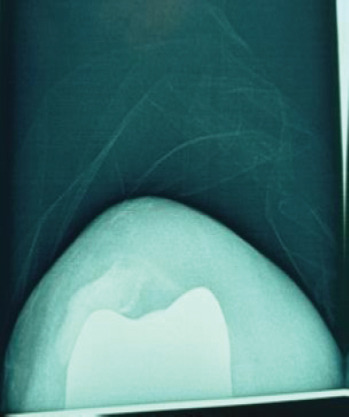

Case report: A 71-year-old Caucasian woman presented to our orthopedic department due to chronic right knee pain, which had worsened over the past year. She was diagnosed with osteoarthritis and was scheduled for a TKA. Three years postoperatively, she returned for examination due to anterior knee pain. Patellar instability was observed and intensive extensor mechanism strengthening and physiotherapy were recommended. Three months later, she presented with severe pain and inability to move her knee. Imaging revealed a fracture and dislocation of the patella. She was surgically treated with lateral release and proximal realignment of the extensor mechanism, according to Insall procedure, with great post-operative outcome.